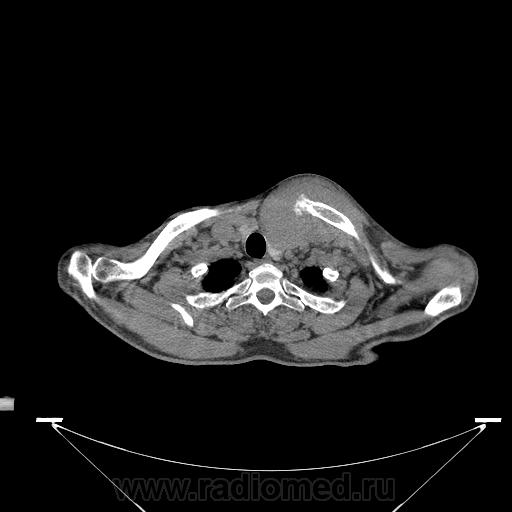

Миелома (плазмоцитома).

Недавний случай. Подтвержден гистологически.  По сцинтиграфии дополнительные очаги гиперфиксации РФП с некоторых ребрах и крестцово-подвздошных сочленениях.